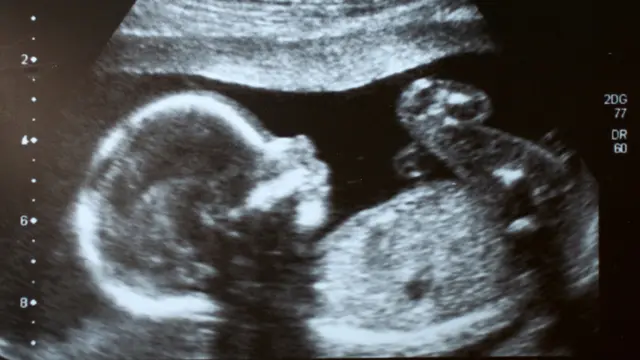

Por ejemplo, la aparición del ultrasonido, el método que se sigue utilizando hoy para poder visualizar el feto dentro del cuerpo de la madre.

"Hasta ese momento nadie había podido observar un feto vivo que respirara. El ultrasonido nos permitió mirar dentro del útero por primera vez, ver al pequeño y poder notar si tiene algún problema", resaltó Harrison.